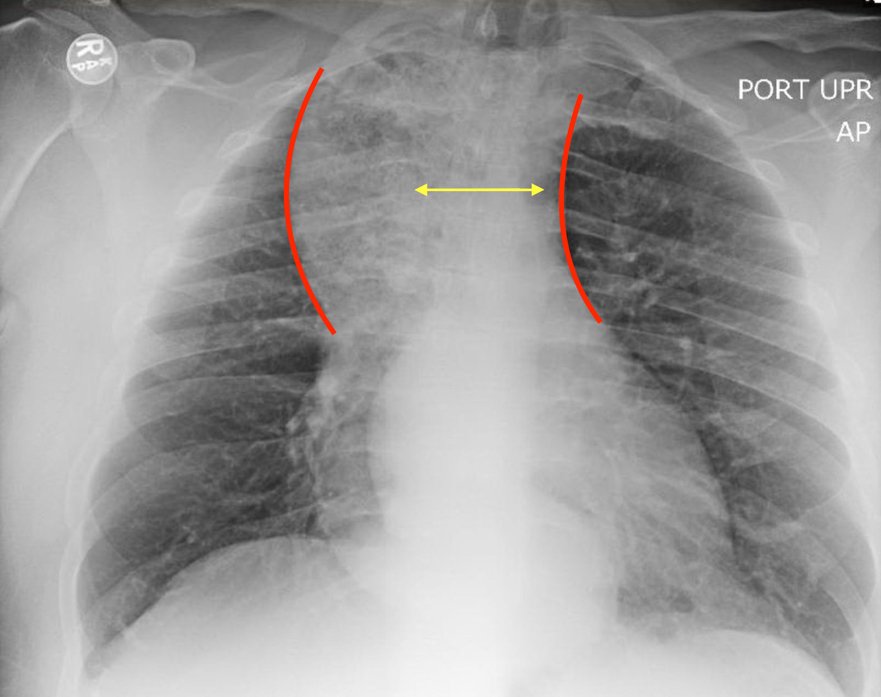

The chest X-ray demonstrated a markedly widened mediastinum (red brackets), raising concern for thoracic aortic aneurysm/aortic dissection, which prompted labs and contrast-enhanced computed tomography (CT) of the chest. The CT revealed a dilated proximal esophagus that narrowed distally (yellow tracing and red arrow), with particulate material, mass-effect on the trachea (purple outline), and bilateral patchy opacities suggesting aspiration. Barium esophagram showed a drastically dilated esophagus filled with contrast (yellow arrow), terminating into the classic “bird’s beak sign” (red arrow) at the lower esophageal sphincter (LES). Esophageal manometry later confirmed achalasia, proving that widened mediastina can have unexpected etiologies.